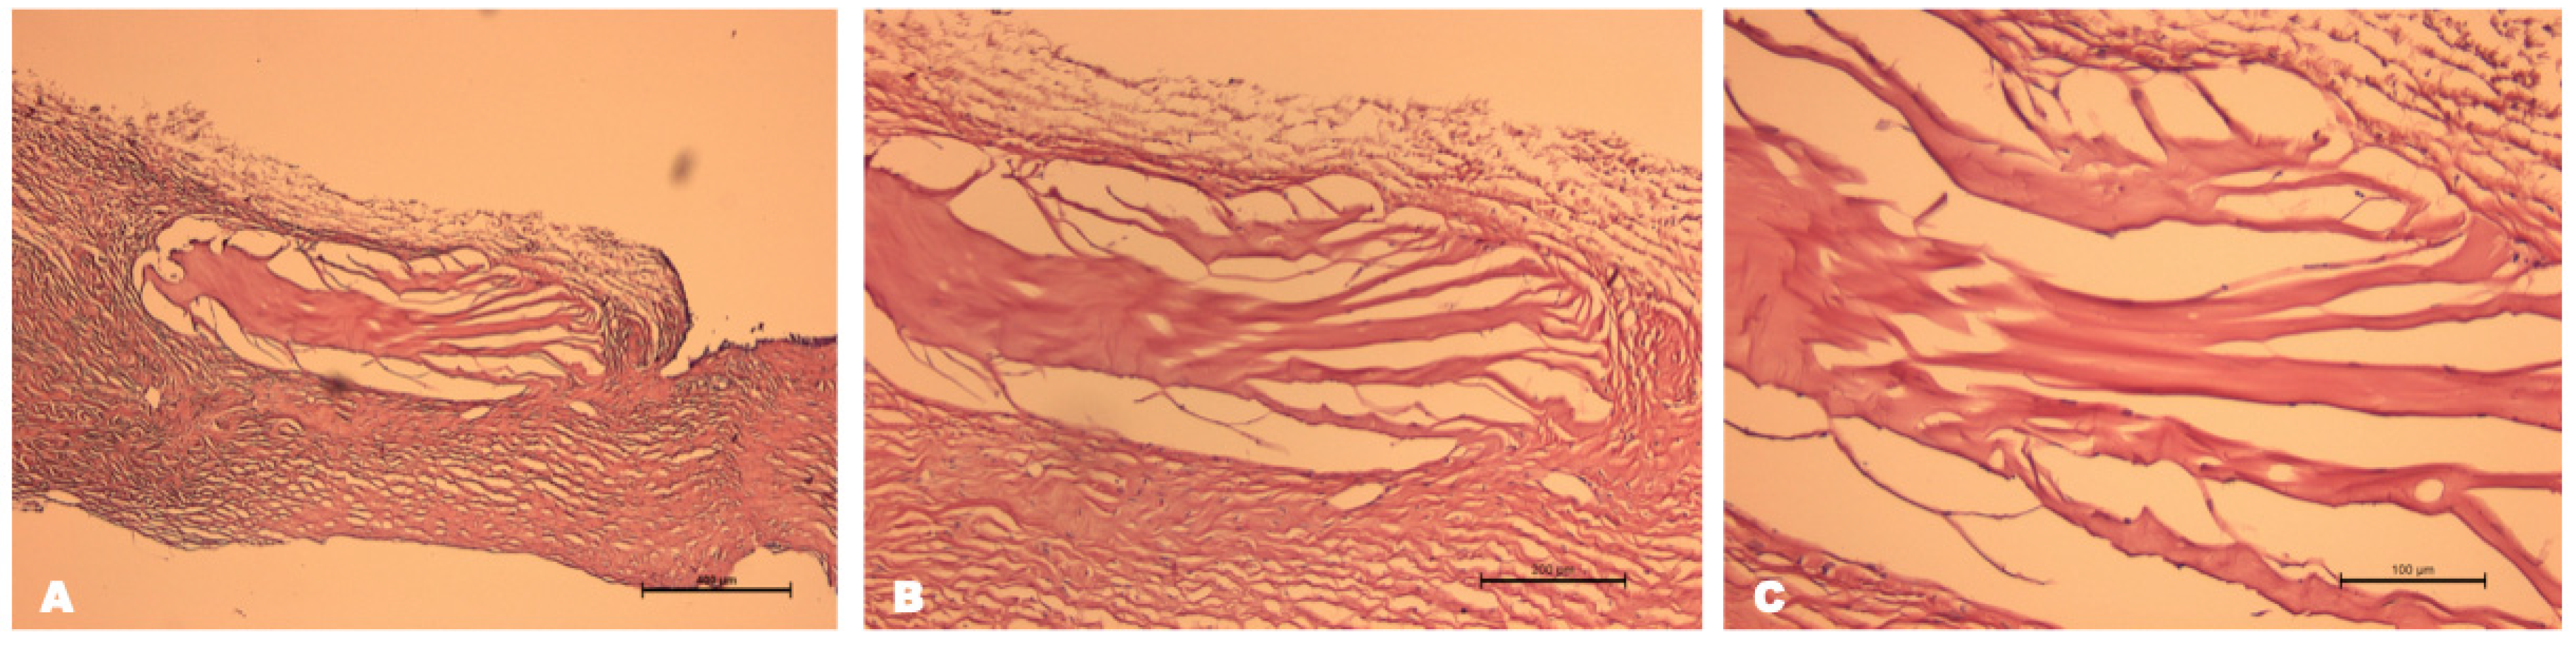

The cornea remained transparent after limbectomy with collagen hydrogel implantation, and there were no signs of immune rejection, such as corneal edema, epithelial defects or infiltration. A small area of focal reaction in the form of blood vessel ingrowth was detected at the site of the knotted sutures (Figure 5). Histologic examination of the enucleated eye was performed one month after the operation. The histologic section revealed a collagen membrane that was covered by conjunctival epithelium. In addition, the migration of single cells with large hyperchromic nuclei inside the implant was detected (Figure 6A). No signs of inflammation, leukocyte infiltration or fibrosis were observed (Figure 6B). As a result, it can be concluded that the collagen biomaterial used is biocompatible and does not cause a toxic reaction when transplanted into the limbal zone.

Figure 6. Histological section of limbal area with the Viscoll collagen membrane. In the thickness of the collagen implant, single migrated cells with hyperchromic nuclei were observed. Stain: hematoxylin and eosin. (A) Scale bar: 400 μm; (B) scale bar: 200 μm; (C) scale bar: 100 μm.

Biomedicines 12 00101 g006